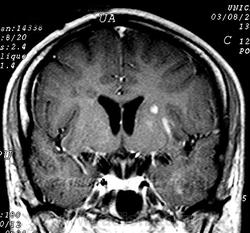

ГМ. Рассеянный склероз 3. +

Рассеянный склероз